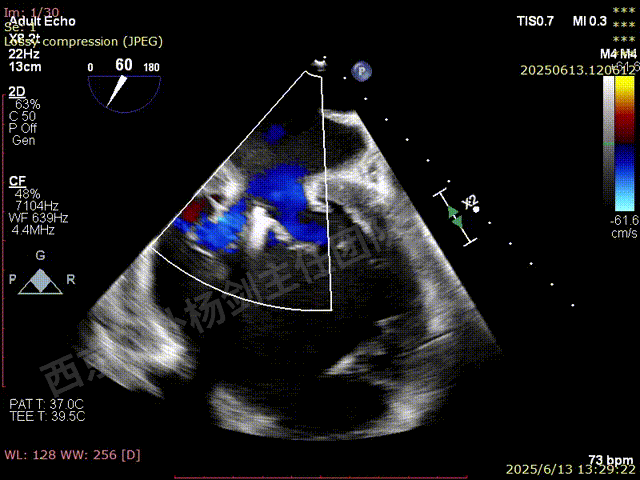

TEER术前超声评估

二尖瓣后叶栓系严重,前叶相对错位,反流束沿2区分布广泛,2偏3区处存在反流。

反流宽度至少23mm,因影像调整困难,考虑实际反流更宽。